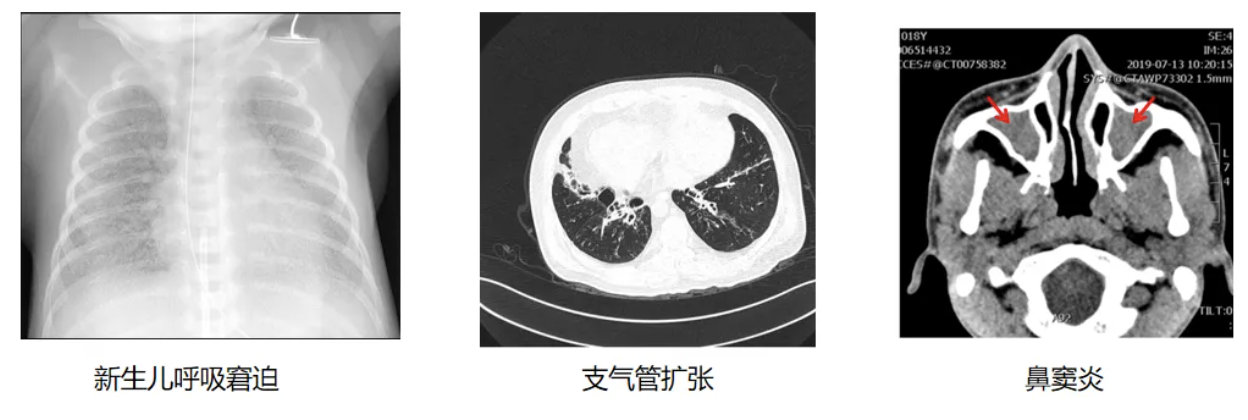

在临床上,如果患者符合以下特征:足月儿发生新生儿呼吸窘迫,早发的支气管扩张,反复不愈的鼻窦炎等症状,就应该考虑进行PCD相关的检查。在询问病史时,以呼吸病史为主,兼顾其他系统。同时应注重询问家族史,家系中有无类似情况。